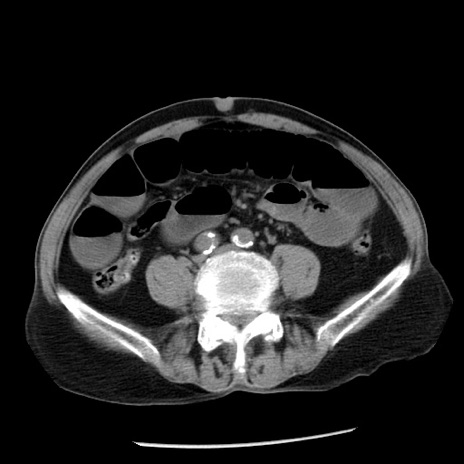

症例26(横断像)

【症例】80歳代男性

【主訴】嘔吐

【現病歴】昨晩2回嘔吐あり、今朝になっても嘔吐あり。来院。

【既往歴】胃潰瘍

【身体所見】意識清明、BT 37.6℃、BP 166/95mmHg、HR 100bpm、SpO2 97%、腹部:平坦・軟、腸蠕動音聴取良好、圧痛なし。

【データ】WBC 21900、CRP 1.46